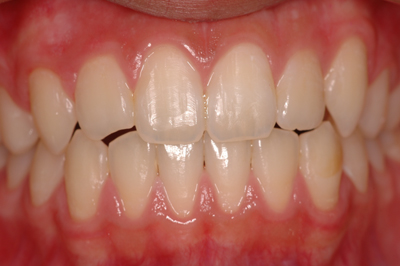

装着前

装着後